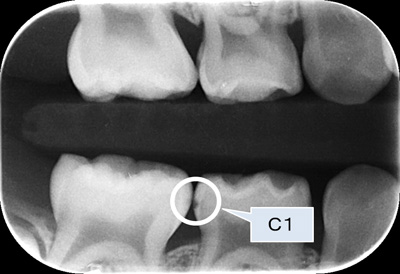

C1とは

C1とは、エナメル質に留まる約1mmの穴(実質欠損)がある場合を言います。

かつては、早期発見早期治療が望ましいとの考えで、C1も治療の対象としていた時代もありましたが、現在は、C1も定期的な観察を行っていくことが望ましいことが分かっています。

当院では、C1は可能な限り、歯を削らずに、予防処置を行った上で、注意深く観察していきます。

下のレントゲンはバイトウィング法(咬翼法)という撮影法で、隣接面(歯と歯の間)のう蝕(むし歯)をチェックする方法で、C1のう蝕(むし歯)を示しています。

しかし、定期的な観察を行わないとすぐに、次のステップC2(象牙質まで進行した状態),C3(歯髄まで進行した状態)へ進むことも知っておいてください。